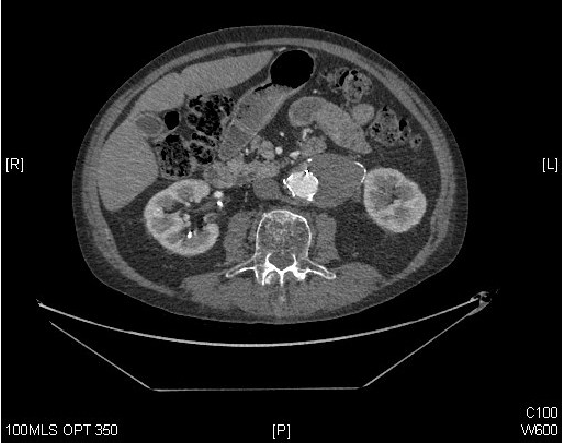

双相腹部-骨盆CT扫描报告(图1):“…主动脉瘤囊自上次扫描后略有减少…已知的II型内渗蛋白没有变化。然而,异质腰肌集合的大小增加了,这似乎与(主要是血栓形成的)动脉瘤囊之间有联系。”

图1:腹部CT显示主动脉内有对比,存在EVAR支架和血栓形成的动脉瘤囊。